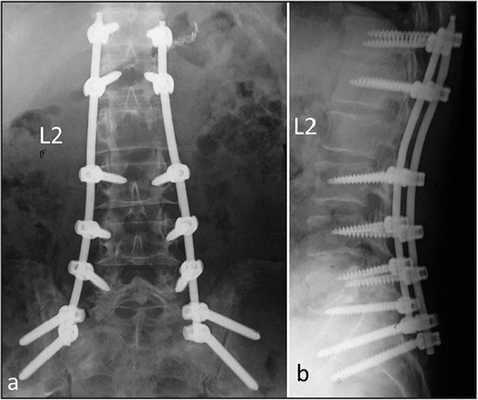

Стабилизацией называется хирургическая установка специальных приспособлений на позвоночник, которые фиксируют части позвонка или смежные ниже- и вышележащие тела, препятствуя их смещению по отношению друг к другу и ликвидируя деформирование хребтовой оси. Проще говоря, стабилизирующая операция предполагает коррекцию положения, предотвращение нестабильности и повышение опороспособности позвоночного столба на любом из его сегментарных уровней. Процедура сложная, длится от 2,5 до 4 часов, выполняется под общим наркозом.

Стабилизационная система на рентгене.

В большинстве случаев проблемный сегмент стабилизируют с помощью металлоконструкций, чаще представленных транспедикулярными системами и пластинами с винтами из высокотехнологичных сплавов металла. В хирургии такая техника называется инструментацией позвоночника. Кроме металлоконструкций, для стабилизации также могут быть применены полимерные устройства, сделанные, например, из углеводородного волокна или резорбирующегося высокомолекулярного биополимера. К отдельной разновидности стабилизирующих вмешательств, которые не причисляют к инструментации, относят установку кейджей имплантатов межпозвоночных дисков.

Кейджы межпозвоночных дисков поясничного отдела.

В преобладающем количестве подобные операции заключаются в достижении полного обездвиживания патологических уровней за счет прочного скрепления двух или более позвонков ригидными конструкциями. Это позволяет позвонкам с течением некоторого времени (от 3 до 6 месяцев) срастись между собой и образовать единый неподвижный костный блок. То есть, на прооперированном поле подвижность между позвонками будет заблокирована, а человек сможет нормально двигаться и ходить, не испытывая при этом боли и прочих неврологических расстройств.

Если выполняется одноуровневая фиксация, искусственно созданная обездвиженность будет неощутимой. При многоуровневой технике стабилизации, что требуется не так уж и часто, позвоночник в определенных местах утратит гибкость, из-за чего некоторые элементы движений станут выполняться несколько в ограниченной амплитуде.

Современные достижения в области методов спинальной фиксации не ограничиваются сугубо на жестком соединении и полном сращении позвонковых тел. Сегодня благополучно ставят различных форм и размеров динамические стабилизаторы без создания спондилодеза, цена на них выше, чем на традиционные неподвижные конструкции. Внутренние динамические системы дают возможность максимально сохранить движения между поверхностями тел позвонков, при этом полностью ограничивают их выход за пределы физиологических значений подвижности.

Стабилизация поясничного отдела.